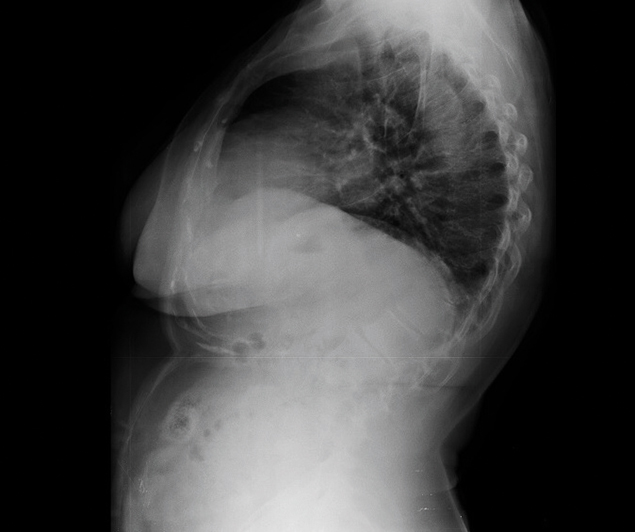

En sık rastlanan postür bozukluklarından biri olan kifoz (kamburluk) ve skolyoz (omurganın sağa ya da sola doğru eğrilmesi) rahatsızlıklarını bir arada yaşayan emekli öğretmen Semra Çağlar, ağrılarından fizyoterapist Elif Akıncı’nın geliştirdiği rubatonik pilates sayesinde kurtuldu. Yaklaşık 10 yıl önce rahatsızlığını fark eden, ablasında ve teyzesinde de aynı hastalık olduğu için bunun kader olduğuna inanarak tedaviyi denemeyen Semra Hanım, Elif Akıncı Pozitif Yaşam Merkezi’ne adım attığı andan itibaren omurga problemlerinin giderilebileceğini anlamış ve bu hastalıkla savaşmaya başlamış. Fizyoterapist Elif Akıncı’nın geliştirdiği egzersiz metodu rubatonik pilates ile ağrıları oldukça hafifleyen, 60 derecelik kifozu 30 dereceye gerileyen ve skolyozunda da ciddi bir düzelme olan Semra Hanım, Elif Akıncı ile tanışmasını, tedavi sürecini ve yaşadığı değişimi şöyle anlatıyor:

Rahatsızlıklarım nedeniyle sırtımda çok ciddi ağrılar vardı. Öyle ki ağrılar yüzünden sırt üstü yatamıyordum. Çok acı çekiyordum. Kifozdan dolayı mide rahatsızlıklarım da başlamıştı. Şubat ayında egzersizlere başladık. Mayıs ayına kadar aralıksız devam ettik. 15. seanstan itibaren bende hızlı bir değişim oldu. 60 derecelik kifozum 30 dereceye kadar geriledi. Doktorum bile çok şaşırdı. Hatta bu sonuç karşısında Elif Hanım ve diğer fizyoterapist arkadaşlar sarıldık, kucaklaştık. Bunun yanı sıra skolyozumda da gerileme olduğunu öğrendim.”